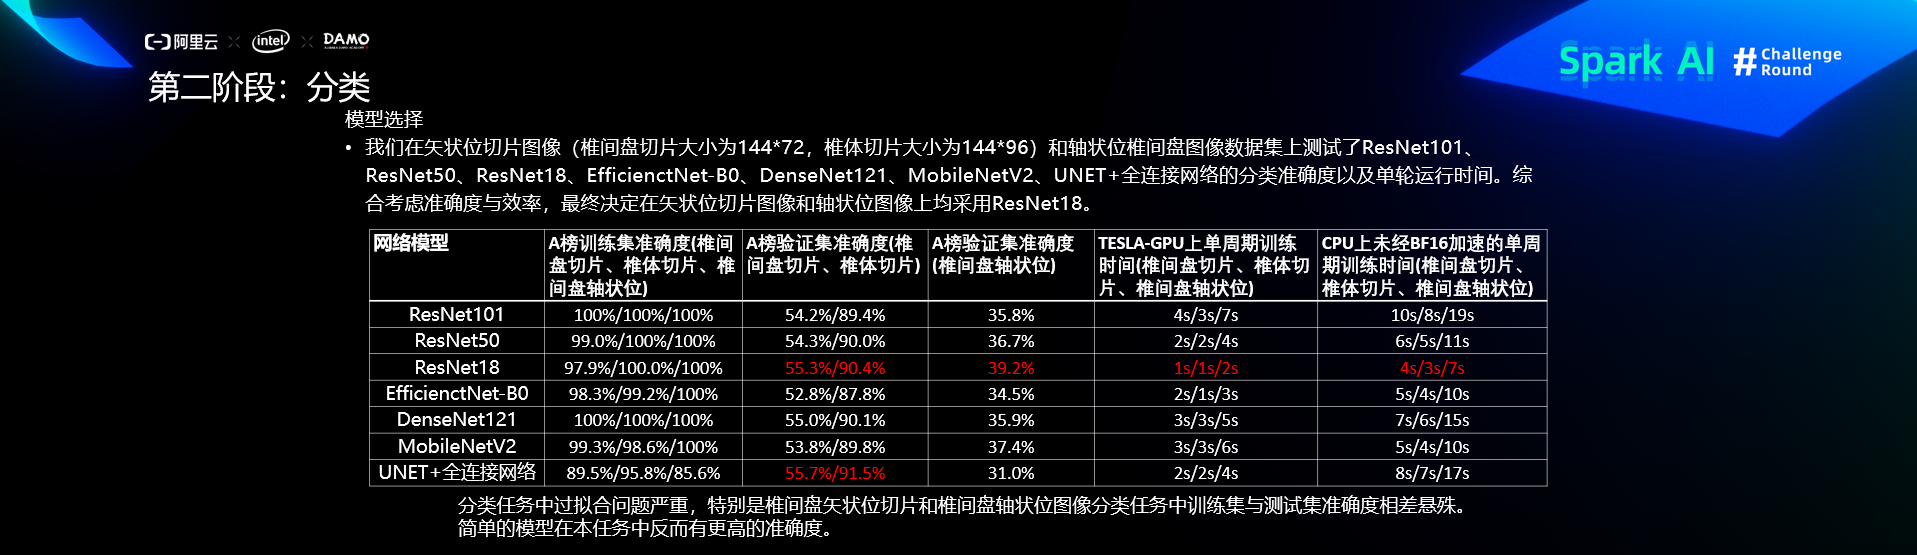

第二阶段:分类

预处理

分类算法